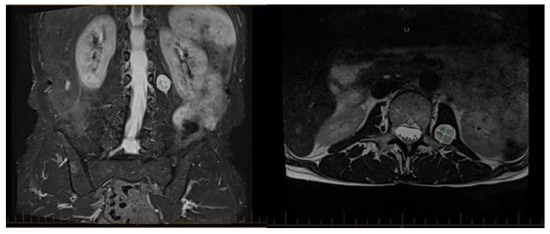

- Perica, E.; Sun, Z. Patient-specific three-dimensional printing for pre-surgical planning in hepatocellular carcinoma treatment. Quant. Imaging Med. Surg. 2017, 7, 668. [Google Scholar] [CrossRef]

- Bernhard, J.-C.; Isotani, S.; Matsugasumi, T.; Duddalwar, V.; Hung, A.J.; Suer, E.; Baco, E.; Satkunasivam, R.; Djaladat, H.; Metcalfe, C.; et al. Personalized 3D printed model of kidney and tumor anatomy: A useful tool for patient education. World J. Urol. 2016, 34, 337–345. [Google Scholar] [CrossRef]